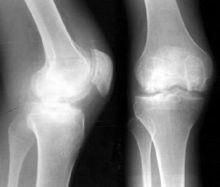

膝關節腫脹,關節積液,晨僵及久坐後有膠著現象,關節伸屈功能障礙,跛行,功能受限,伸屈活動有彈響聲,在下台階、久立時膝關節症狀加重,部分患者可見關節積液,局部有明顯腫脹、壓縮現象,膝其中關節前內側條索樣腫塊伴伸膝障礙,膝關節周圍骨贅形成,關節周圍伴有骨質疏鬆與骨質硬化。關節面毛糙不平,其內側脛股關節面受累明顯,關節間隙變窄,其中多數會發生內側間隙狹窄,髕骨骨刺形成。

膝蓋骨質增生膝關節骨質增生為臨床常見病、多發病,多發於中老年以上患者。臨床以雙膝關節劇烈疼痛、行走無力、活動受限、X檢查示雙膝關節骨質增生為特徵。本病手術適應證要求較高,且效果不好,給治療帶來了很大的困難。